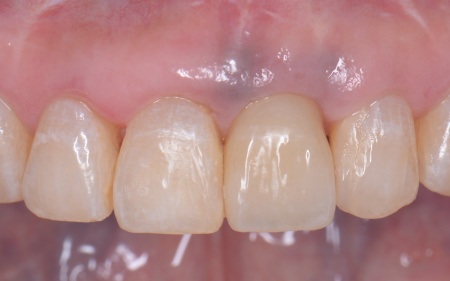

50代女性 インプラント・矯正・被せ物治療で見た目と噛み合わせを改善した症例

④矯正終了後に右上下奥歯の合わなくなった被せ物を除去し、自然な白さで強度もあるジルコニアセラミッククラウンを装着する。

最後に装着したジルコニアセラミッククラウンが歯に合っているか、噛み合わせに問題がないかを確認し、治療を終了しました。